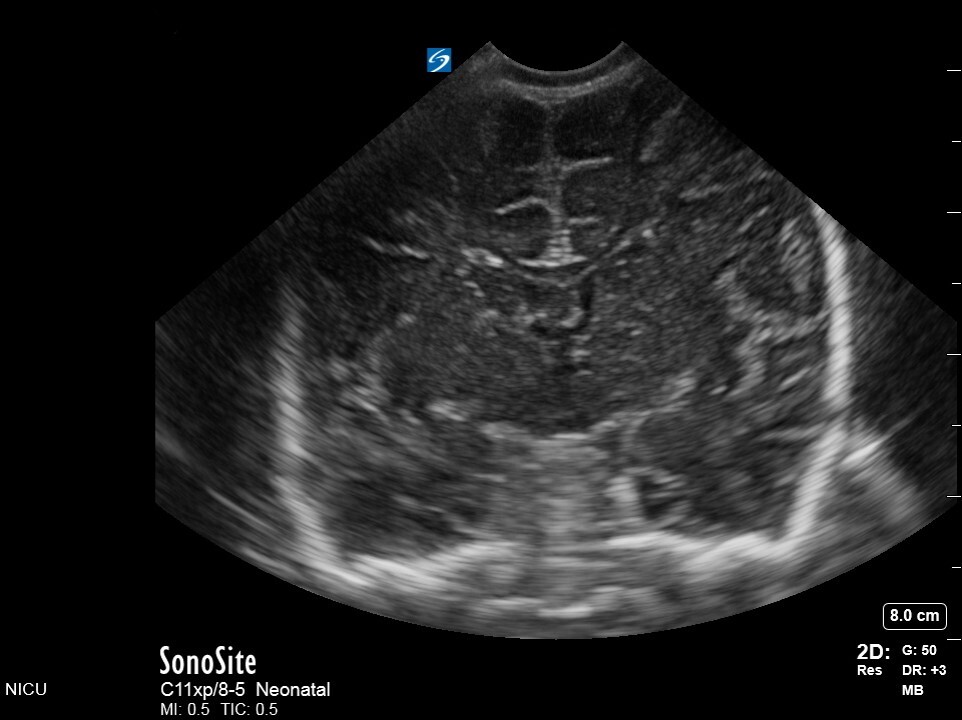

Neonatology C3 1 Image